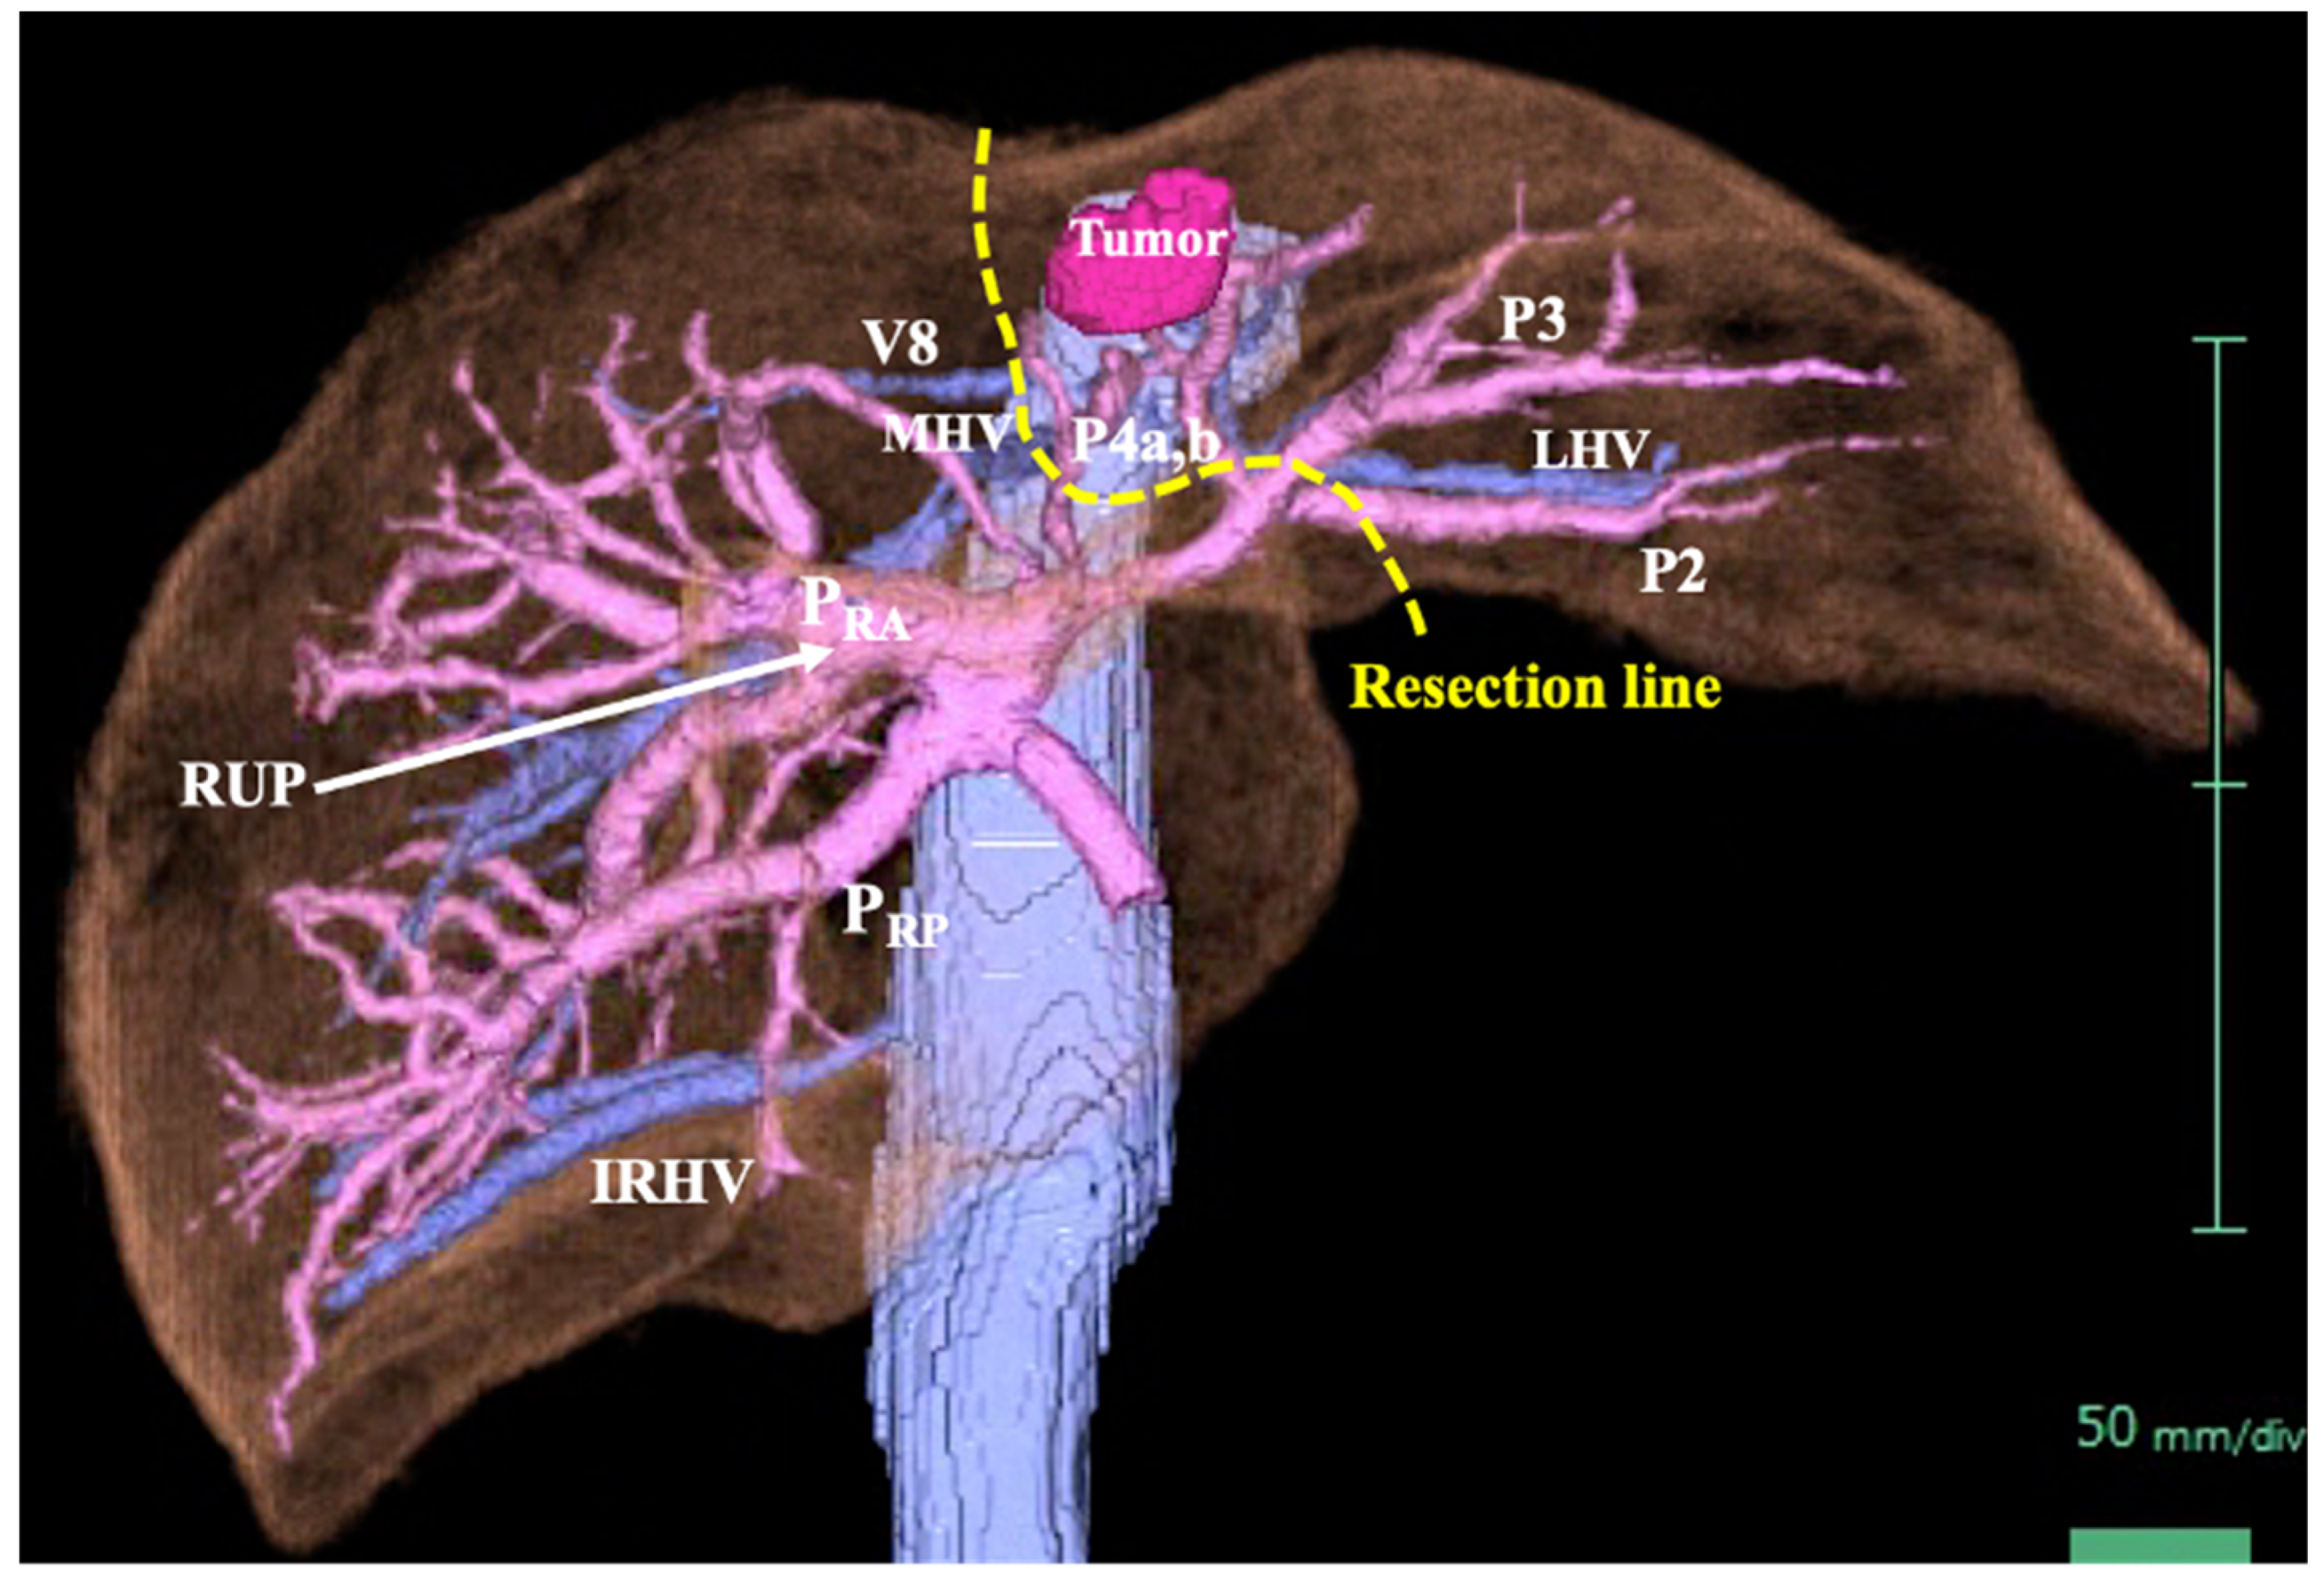

Figure 4. Three-dimensional computed tomography. The tumor (2.4 × 2.0 cm) was in the left lobe of the liver (S2/3/4b). The portal vein had a right posterior branch (PRP), right anterior branch (PRA), and left branch. The PRP branched independently. The left branch branched into P2 and P3 after two P4 branches separated. The PRA was connected to the right umbilical portion (RUP). A right inferior hepatic vein (IRHV) and V8 were present. The middle hepatic vein (MHV) and left hepatic vein (LHV) were normal. The planned resection line is indicated by the yellow dotted line.

A 69-year-old man was referred for evaluation of a liver tumor detected on abdominal ultrasonography performed for nonalcoholic steatohepatitis follow-up. Blood testing showed elevations in concentrations of aspartate transaminase (56 U/L), alanine transaminase (51 U/L), and protein induced by vitamin K absence-II (224 mAU/mL). Other tumor markers and hepatitis virus markers were negative. The indocyanine green retention rate at 15 minutes was 15.2% and Child–Pugh score was 5 points (class A), suggesting good hepatic function. Computed tomography (CT) showed a 2.4 × 2.0 cm hypodense mass in the left lobe of the liver (S2/3/4b) which exhibited early arterial enhancement and washout (Figure 1). Hepatocellular carcinoma was highly suspected. In addition, the ligamentum teres was connected to the right anterior branch of the portal vein, and the gallbladder was located to its left, indicating RSLT (Figure 2). On magnetic resonance imaging, the mass was low signal intensity on T1-weighted images and high signal intensity on T2-weighted and diffusion-weighted images; contrasted imaging using gadolinium ethoxybenzyl diethylenetriamine penta-acetic acid revealed a perfusion defect in the mass in the liver phase (Figure 3). Three-dimensional CT (Synapse Vincent®︎; Fujifilm Medical, Tokyo, Japan) demonstrated right posterior, right anterior, and left branches of the portal vein. The left branch branched into P2 and P3 after two P4 branches separated. A right inferior hepatic vein and V8 were present (Figure 4). Magnetic resonance cholangiopancreatography revealed that the bile duct system was trifurcated into right posterior, right anterior branch, and left branches (Figure 5). After the pertinent anatomy was clarified and the preoperative evaluation was completed, we elected to perform laparoscopic extended lateral sectionectomy.

Our patient exhibited an independent posterior branch of the portal venous system, which is present in more than half of patients with RSLT [1,2,5]. Shindoh et al. classified RSLT into three types based on portal branching pattern: bifurcation, trifurcation, and independent right lateral (posterior) type [1]. In contrast, Terasaki et al. classified patients into four types: one bilateral ligamentum teres group and three RSLT groups (bifurcation, trifurcation, and independent posterior branch types) [5,7]. The newer Terasaki system may become the standard in the future. Regarding hepatic veins in patients with RSLT, a thick vein running along the ventral-dorsal segment border of the anterior sector and a developed V8 are likely to be present [1,5]. Our patient exhibited a developed V8. Because the middle hepatic vein (MHV) in patients with RSLT tends to be atrophic and displaced medially, the V8 may be misidentified as the MHV and should be treated with caution [5]. As for the hepatic artery, most bifurcate and branch normally in patients with an RSLT, as in our patient [1,8].